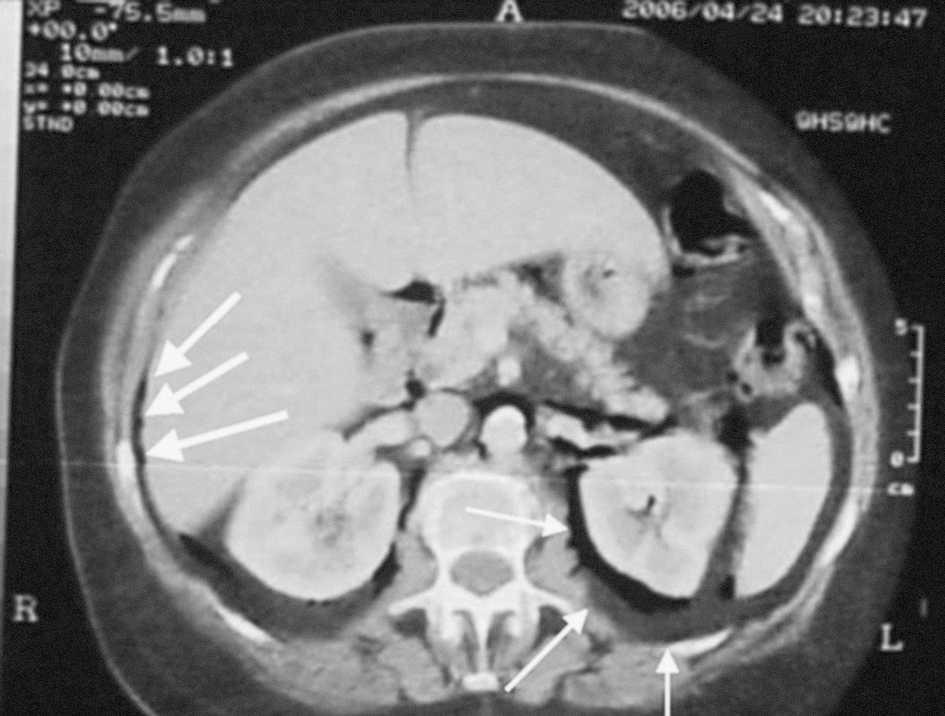

Mujer de 74 años que consulta por lumbalgia izquierda irradiada a miembro inferior izquierdo y dolor tenue en fosa ilíaca izquierda sin signos de irritación peritoneal ni fiebre, tras 15 días de tratamiento con antiinflamatorios no esteroideos, prescritos en dos servicios sanitarios extrahospitalarios. En el servicio de urgencias de nuestro centro se le practicó analítica de orina y radiografía de tórax (normales), analítica sanguínea (13.700 leucocitos y fórmula normal). En la radiografía de raquis lumbar, además de importante espondiloartrosis, se objetivó aerograma en localización atípica (fig. 1). Con el diagnóstico radiológico de neumorretroperitoneo, se le realizó de urgencia una tomografía computarizada abdominopelviana con contraste, que lo confirmó (fig. 2; flechas finas); además, se visualizaba mínimo neumoperitoneo (fig. 2; flechas gruesas) y enfermedad diverticular de sigma, cuya perforación se evidenció durante el ingreso. La evolución fue favorable con tratamiento conservador y desapareció la imagen en la revisión en consultas externas.

Fig. 2. Flechas finas: neumorretroperitoneo en espacio pararrenal izquierdo. Flechas gruesas: neumoperitoneo mínimo.

Diagnóstico:Neumorretroperitoneo.